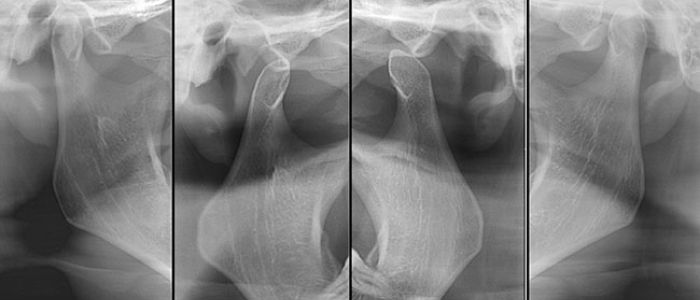

Radiografías Extraorales

Las radiografías extraorales se emplean cuando no es factible obtener información diagnóstica adecuada en las series de radiografías intraorales, es así que son utilizadas para observar un área grande de los maxilares y del cráneo en una sola radiografía. Los exámenes radiográficos extrabucales tienen el propósito de evaluar áreas grandes del cráneo, dientes impactados y patrones de erupción, crecimiento y desarrollo; examinar la extensión de lesiones grandes, traumatismos, articulación temporomandibular. Son de mucha utilidad principalmente en Ortodoncia y Cirugía Bucal.

Existen varias radiografías extraorales entre las cuales se tiene: